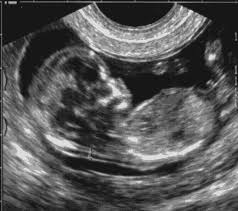

Em São Lourenço/MG (16Dez11), às 18h18min, a Polícia Militar foi acionada a comparecer na Rua Ida Mascarenhas Lage, Bairro Nossa Senhora de Fátima, onde o solicitante A.A.M., 48 anos, relatou que sua filha A.N.M., 22 anos, estava grávida de nove meses e sentiu-se mal no dia 14/12/2011, sendo medicada e liberada no hospital de São Lourenço/MG.

Horas depois, foi consultar com seu médico, sendo que este após examina-la, constatou que seu feto já estava morto a setenta e duas horas. Copiei essa noticia do Popular.net.